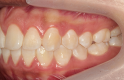

Classe II div 1, articulé croisé postérieur, surplomb accru, déviation de la ligne médiane maxillaire, rotations d'encombrement

Résultats obtenus

- Relation de classe I obtenue

- Guidage fonctionnel des canines des deux côtés

- Articulé postérieur corrigé

- Surplomb et recouvrement normaux obtenus

- Surplomb amélioré

- Lignes médianes coïncidentes

- Bonne inclinaison axiale des incisives

- Courbe de Spee nivelée

- Forme de l'arcade améliorée

- Cas où tous les objectifs du traitement ont été atteints

- Des arcades harmoniques ont été obtenues

État initial

État final